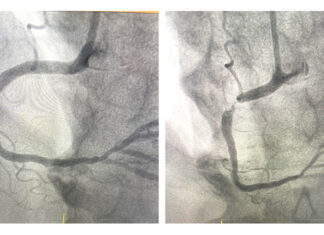

“Secondary prevention means preventing a patient who has already had a cardiac event, such as a heart attack or stroke,...